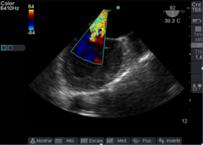

Luego con Doppler Color, analizamos la dirección del chorro regurgitante que es opuesta a la valva comprometida, el tamaño del jet regurgitante y su relación con el área de la aurícula izquierda (AI). Debemos tener en cuenta que el mapeo color del chorro regurgitante está influenciado por parámetros del ecógrafo: ganancia, PRF, límite de Nyquist, y por parámetros fisiológicos: presión arterial, volemia.

Otro factor que afecta el tamaño del chorro es la dirección de éste, los centrales en la aurícula aparecen más grandes con Doppler Color, que aquellos excéntricos que corren sobre la pared auricular, generando un efecto coanda (Figura 15), con un volumen regurgitante muy similar y que por su sola presencia le confiere severidad.

Figura 15 imagen de 4 cámaras medioesofágico con insuficiencia mitral severa, observada con Doppler color (escala 64) con efecto “coanda”, reflujo hacia la pared de AI.

Clasificamos la IM en leve si el área del jet es < 4cm2, o <20% del área de la AI; moderado de 4-8cm2 y severo mayor de 8cm2.